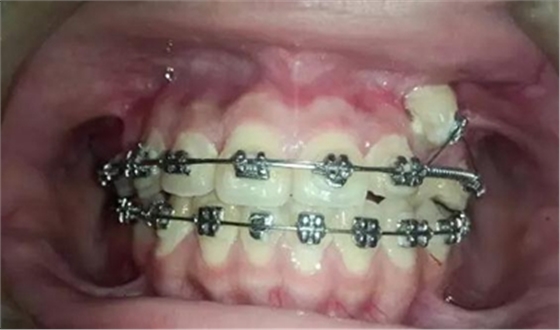

牽引了三四個月尖牙終于長出來了,也遠離了側(cè)切牙

一個月后尖牙下來很多,

加上垂直牽引,尖牙下來的更快了